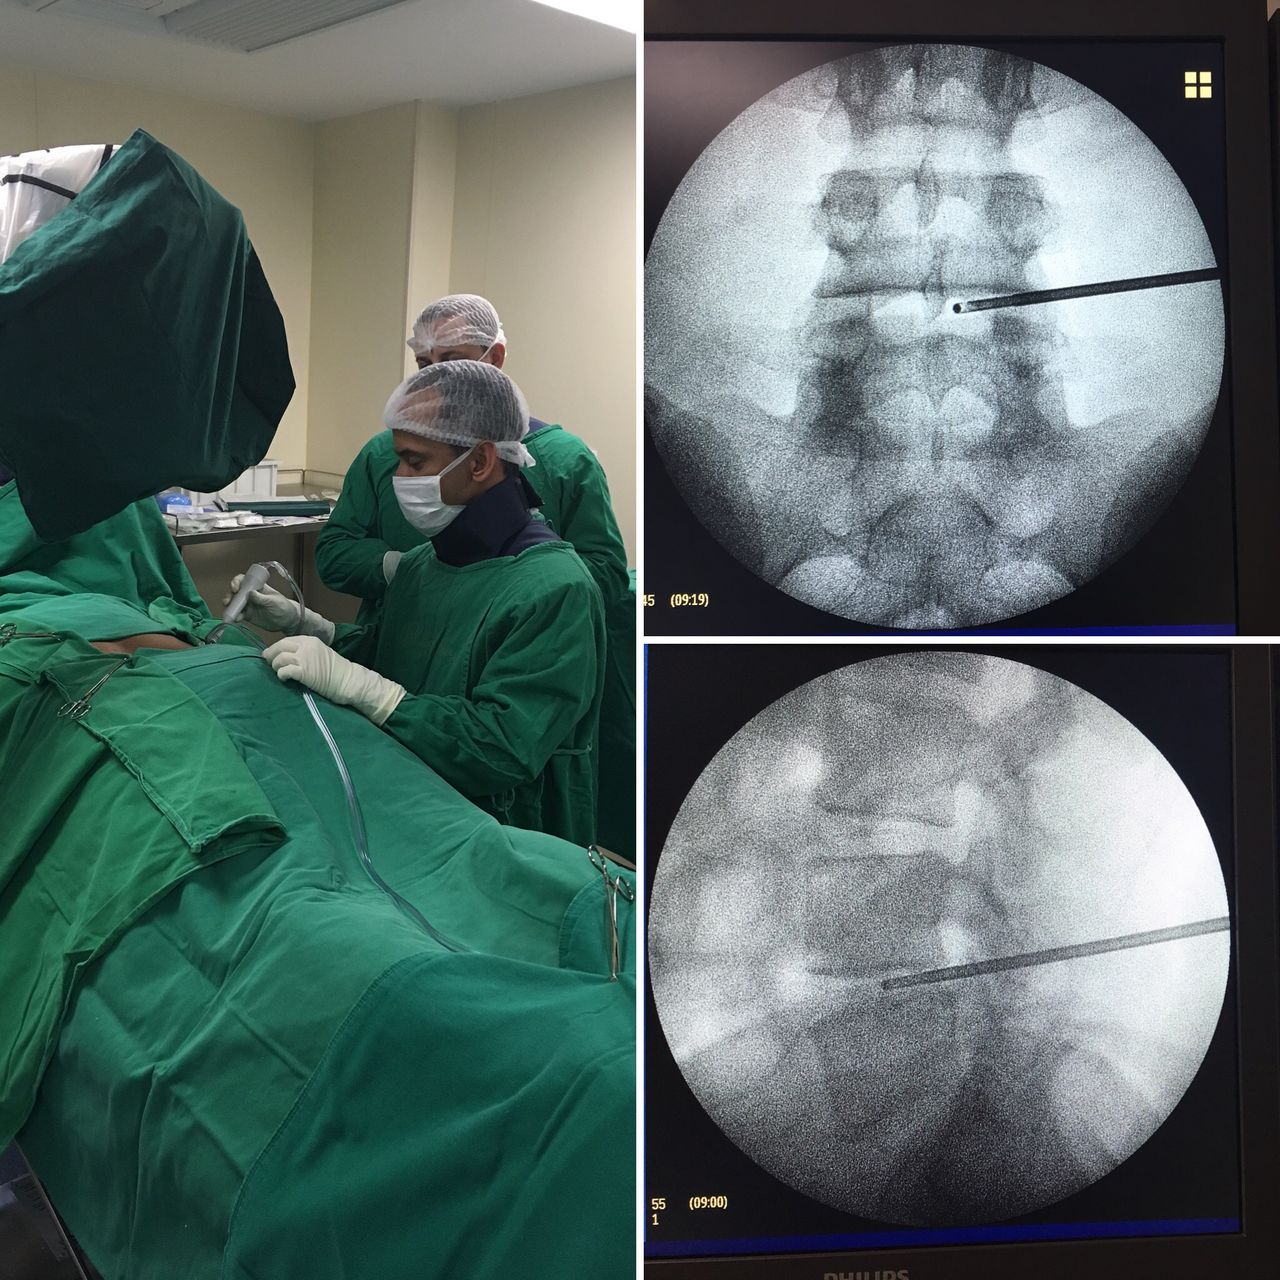

- Cirurgia da coluna vertebral

- Cirurgia endoscópica da coluna

Cirurgia endoscópica da coluna vertebral